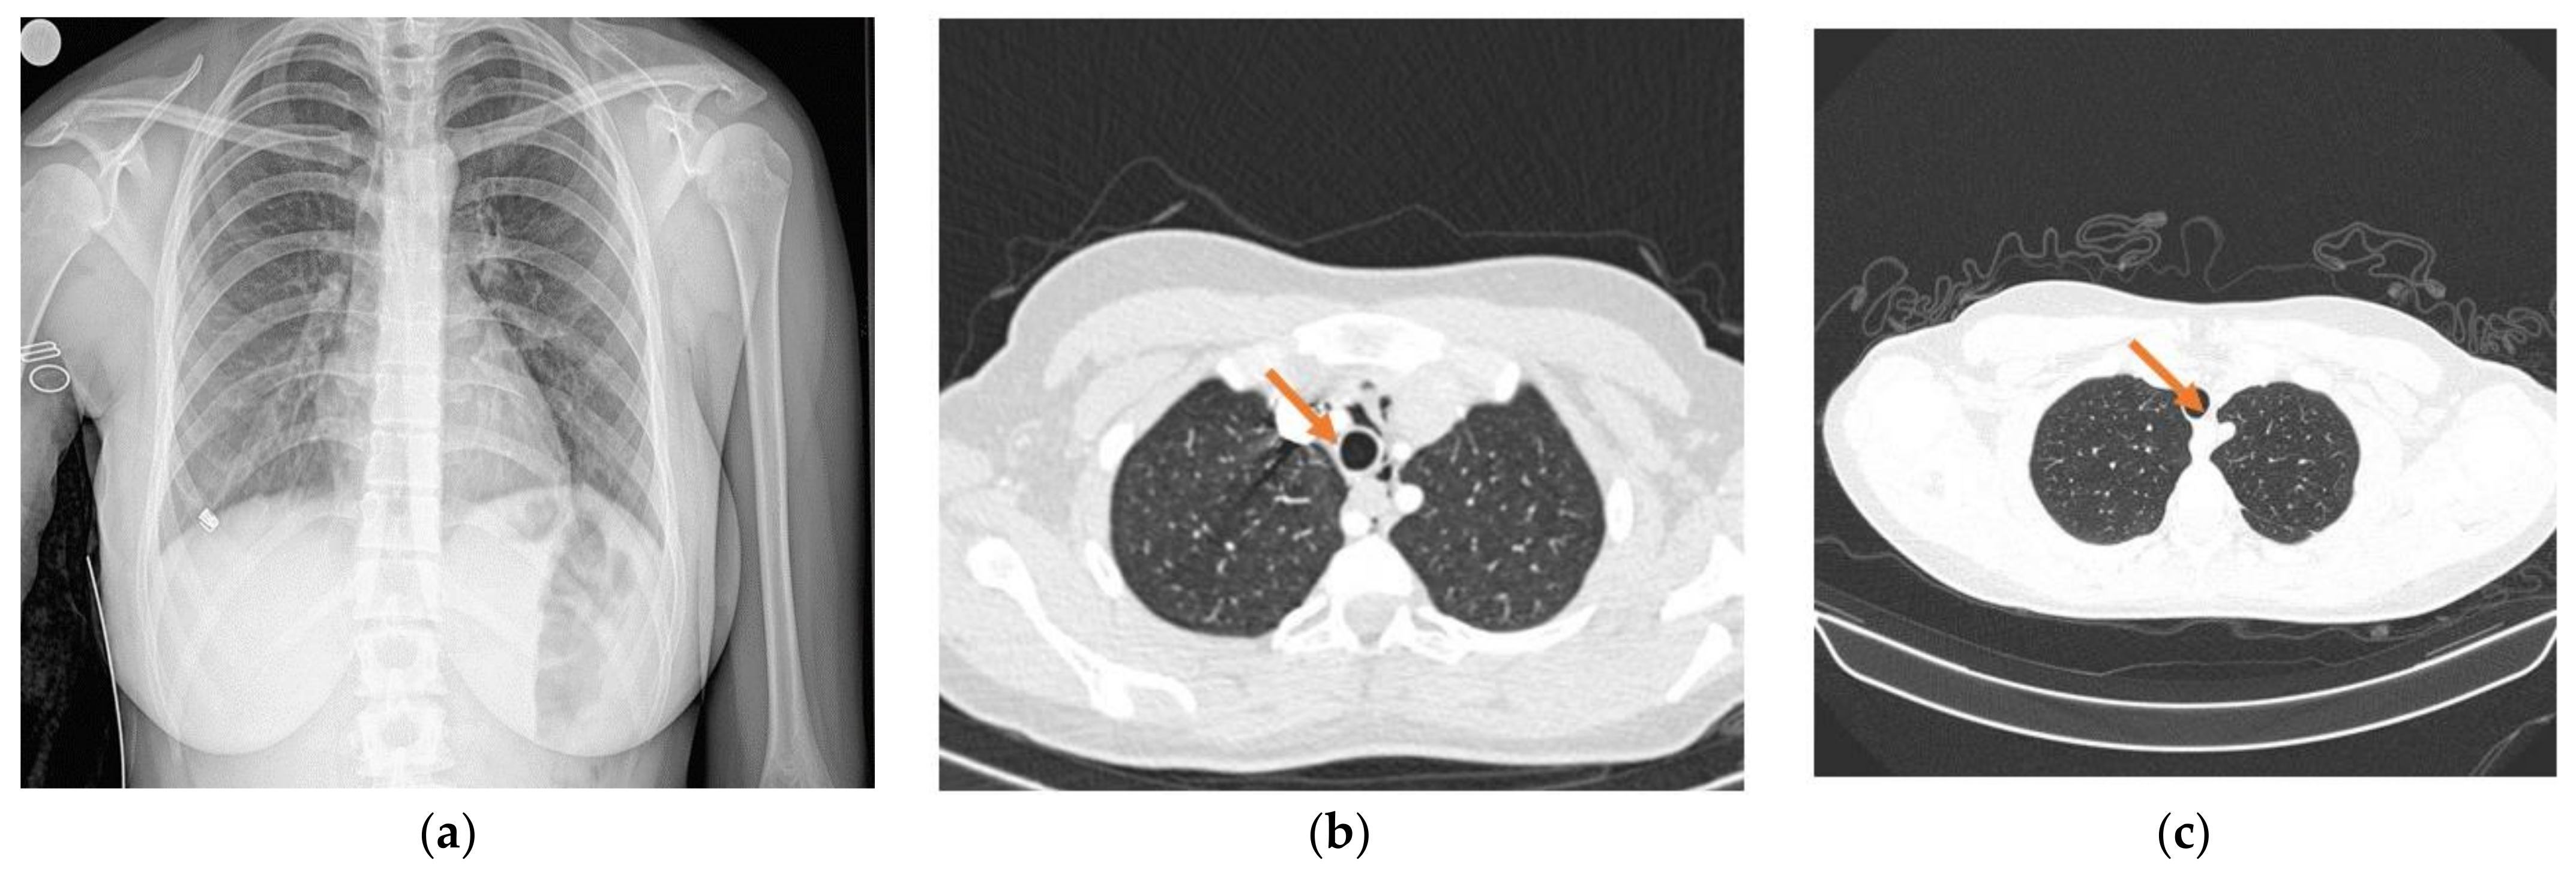

A 16-year-old girl presented to the hospital for ageusia and anosmia lasting for 3–4 days. Her previous medical history was significant for chronic gastritis and hypocalcemia; she had no allergies and was receiving no medication at that point. Given the epidemiological context, she was tested for SARS-CoV-2 infection and was found positive. She had no dyspnea, and the chest X-ray was not significant for SARS-CoV-2 changes (Figure 1a).

Figure 1.

X-ray and CT images. (a) Chest radiograph—no abnormalities (Day 0); (b) chest CT—presence of pneumomediastinum (Day 4); (c) chest CT—pneumomediastinum resolution (Day 11).

The next day she complained of increased chest pain and a moderate degree of dyspnea, which raised the suspicion of a COVID-19-related respiratory complication, including pneumothorax or pneumomediastinum. Since the previous chest X-ray showed no abnormalities, a chest CT scan was recommended in order to identify such findings [10,11]. It showed no direct signs of pulmonary thromboembolism, no pulmonary condensation, and no pleural effusion. A moderate-sized pneumomediastinum (PM) was identified (Figure 1b). A pediatric surgery consult was required. Given the small size of the PM and the good general and respiratory condition of the patient, the recommendations included bed rest, symptomatic treatment, and clinical/radiological observation. Over the admission, her clinical status was good, with intermittent need for O2 delivered by nasal cannula and SpO2 of 96–98% in room air. She required no positive-pressure ventilation or ICU admission. Her vitals were stable at all times with clear lungs on auscultation. A second CT scan was performed after 9 days and showed resolution of the pneumomediastinum (Figure 1c). Additionally, she tested negative for SARS-CoV-2 the same day.